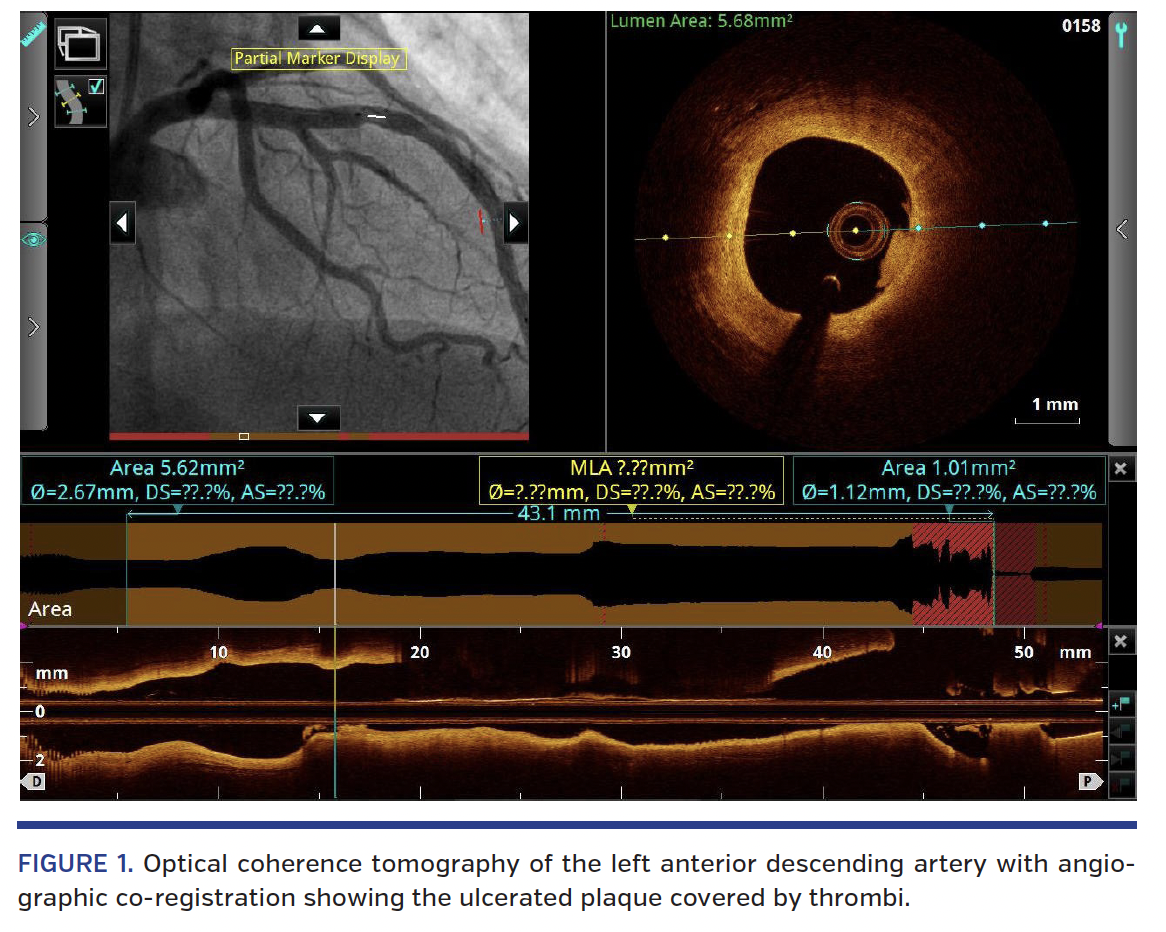

Three-dimensional optical coherence tomography (3D-OCT) with angiographic co-registration was performed and an ulcerated small plaque covered by thrombus was observed (Figures 1-3; Videos 1-2). The amount of thrombus was not excessive and the minimal luminal area was 5.62 mm2, so a conservative management strategy was selected. The patient was asymptomatic at 6-month follow-up exam.